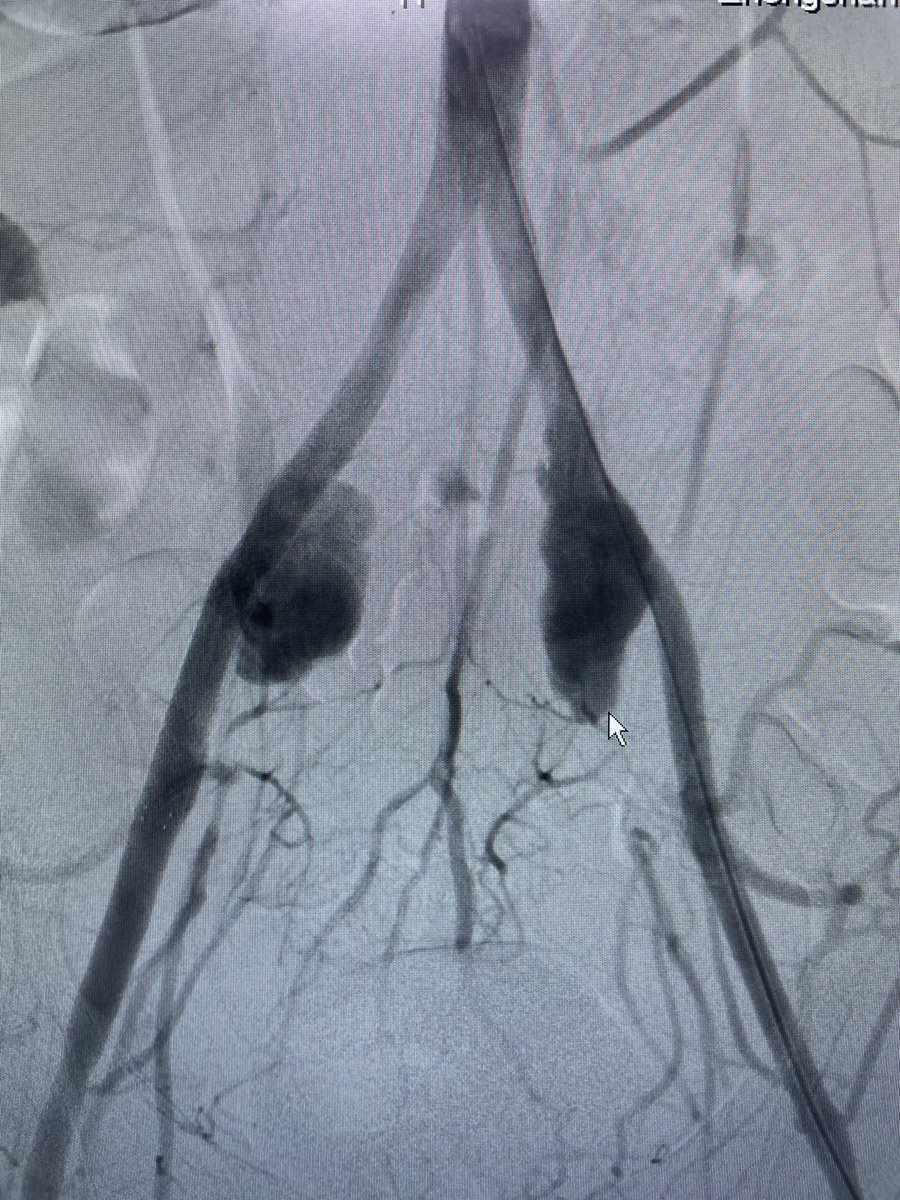

We’re thrilled to be highlighted! At @vasc_ai, our mission is to enhance vascular care through innovation.

Our tool is free to use, and we’re dedicated to creating more cutting-edge solutions that empower clinicians, researchers, and educators.

A quintet of @UofT vascular surgery researchers—led by @TiamFeridooni—are bidding to harness Open AI and refine it into a working model that is functionally vascular specific, capable of being used in clinical practice, research and education vascularspecialistonline.com/vasc-ai-canadi…